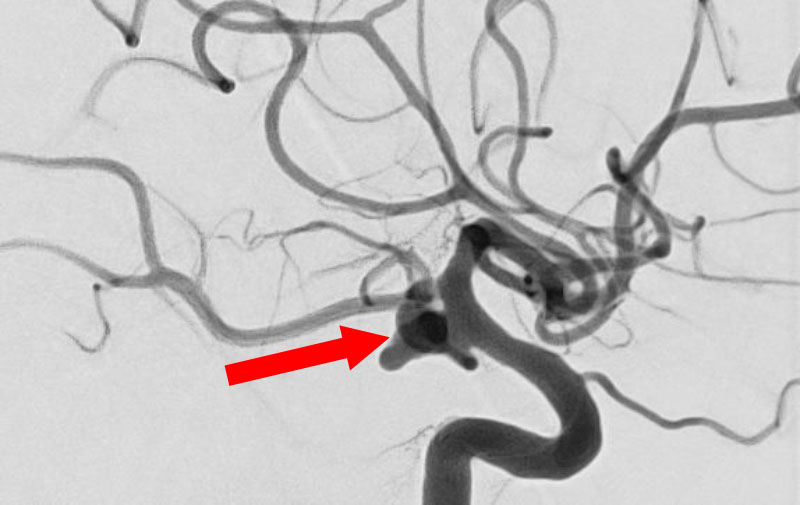

'25年11月

くも膜下出血

右内頚動脈後交通動脈

分岐部動脈瘤破裂

60代

救急外来

No.1593 手術前